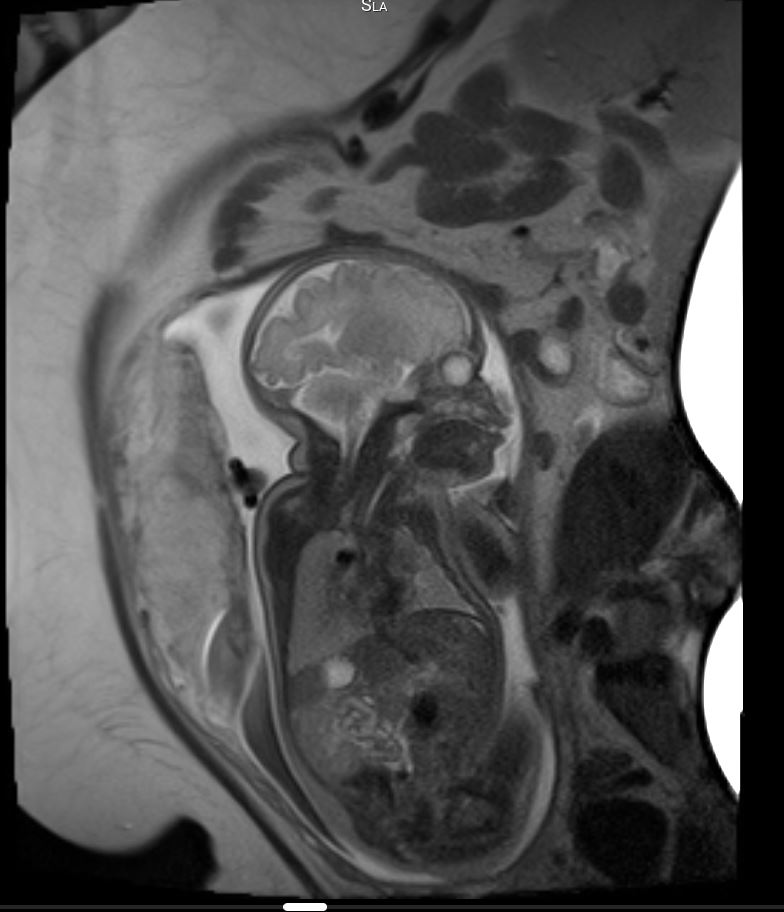

Das fetale MRT (Magnetresonanztomographie) ist ein strahlungsfreies Verfahren, mit dem wir Organe und Strukturen Ihres ungeborenen Kindes besonders detailreich darstellen. Es ergänzt die pränatale Ultraschall-Diagnostik und hilft, Fragestellungen präzise zu klären und die weitere Betreuung zu planen.

- Abklärung von Auffälligkeiten im Ultraschall, z. B. Gehirn, Wirbelsäule, Lunge, Bauchorgane

- Beurteilung von Organreife und Entwicklung, wenn die Sicht im Ultraschall eingeschränkt ist (z. B. mütterlicher Body-Mass-Index, Lage des Kindes)

Unsere Neuroradiologen arbeiten eng mit Pränatalmedizinern, Neonatologen, Pädiatern und Chirurgen zusammen. Modernste Geräte und spezialisierte Protokolle sorgen für hohe Bildqualität – auch bei kindlichen Bewegungen.